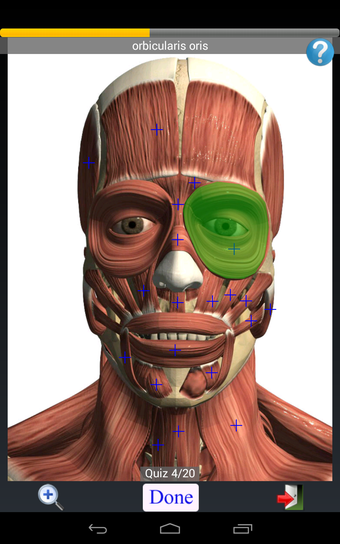

Anatomy Quiz Free es una aplicación de Android de Education Mobile que ofrece una amplia gama de cuestionarios para ayudar a los usuarios a aprender anatomía humana. La aplicación cuenta con más de 500 cuestionarios que ponen a prueba tu capacidad para identificar la ubicación correcta de un objeto dado su nombre. Los cuestionarios se generan a partir de modelos de anatomía 3D virtuales, lo que los hace más atractivos e interactivos. La aplicación es gratuita y no hay versiones premium ni compras dentro de la aplicación.

La aplicación es compatible con los idiomas inglés, francés, español y alemán, lo que la hace accesible para usuarios de diferentes partes del mundo. Las imágenes de alta resolución son nítidas y claras, y la función de zoom con pellizco te permite acercar y alejar las imágenes para una mejor vista. El cuestionario de posición viene con un temporizador, lo que lo hace más desafiante y emocionante. Además, la aplicación tiene una función de transferencia a la tarjeta SD, lo que facilita su transferencia a otros dispositivos.